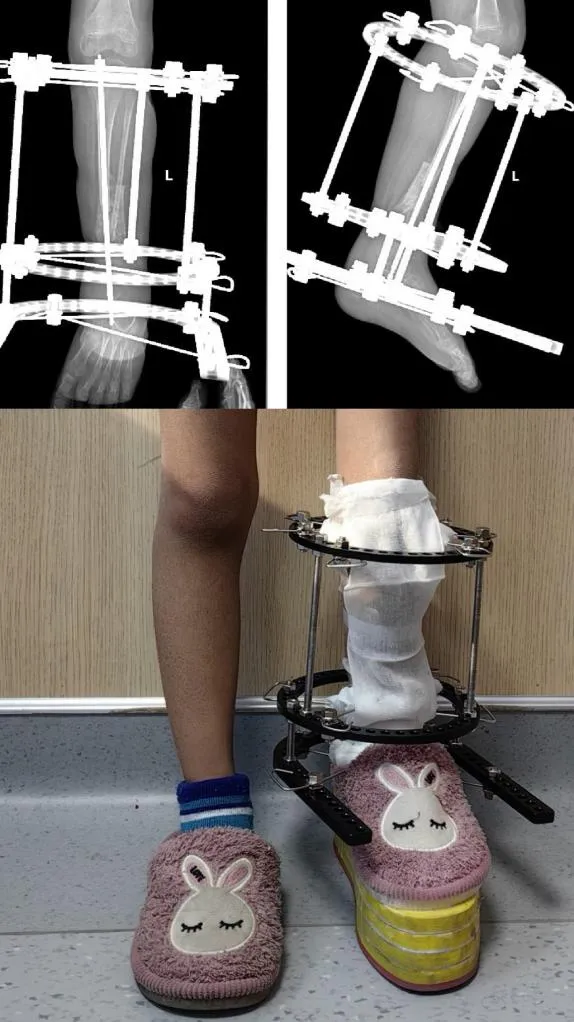

小雨父母多方辗转,带着她来到了郑州市骨科医院。接诊后,郑州市骨科医院小儿骨科的专家为小雨制定了手术方案:“假关节病灶切除+髓内棒固定+自体髂骨移植+环形外固定架加压”“切除病灶、取自体髂骨移植、植入髓内棒、安装外固定架……” 经过数小时的手术,“手术很成功”。

经过几个月的康复训练,复查显示:小雨的胫骨假关节已经实现骨性愈合,下肢力线完美,可以和正常小朋友一样,奔跑、玩耍了!